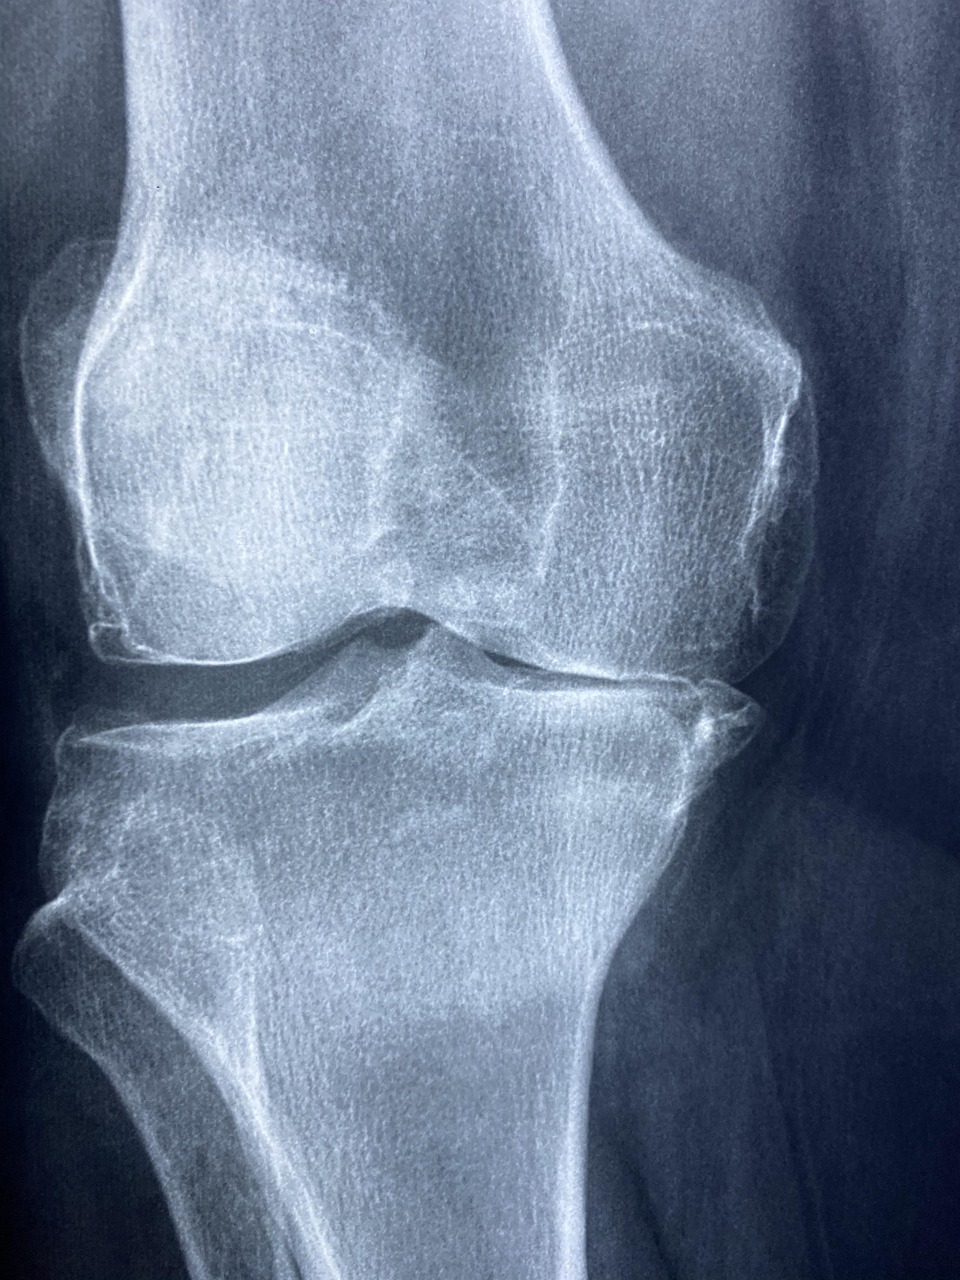

콜라겐은 연골의 주요 구성 성분으로, 관절 건강에 직접적인 영향을 미칩니다. 관절염 환자들을 대상으로 한 연구에서 콜라겐 보충제 섭취 후 관절 통증이 현저히 감소하고 관절 기능이 개선되었고 운동선수들에게 콜라겐을 보충시킨 결과, 운동 후 관절 통증이 감소하고 회복 속도가 빨라졌습니다. 이는 콜라겐이 관절 연골의 재생과 유지에 핵심적인 역할을 하기 때문입니다.